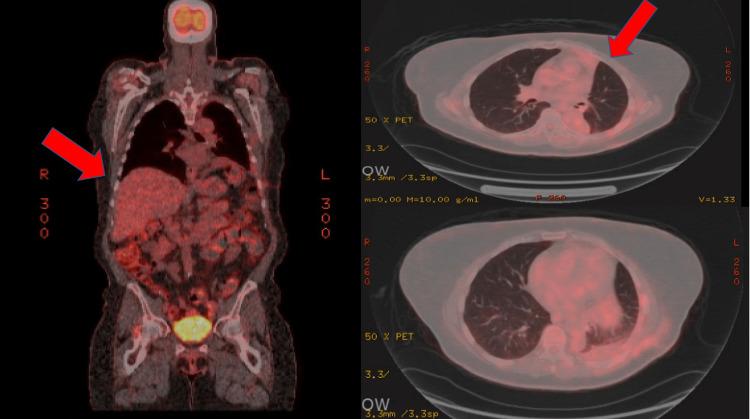

The etiology of complicated pleural effusion can be vast. We present a unique case of an unsuspected metastatic endometrial stromal sarcoma (ESS) in an asymptomatic patient with an incidentally found complicated pleural effusion. A 69-year-old female with no pertinent past medical history was referred to pulmonology for an effusion noted on a routine chest X-ray. Her surgical history was significant for a hysterectomy. At the time of evaluation in the pulmonology clinic, the patient was asymptomatic with stable vital signs. Computed tomography of her chest showed a complex pleural effusion which was drained by cardiothoracic surgery. Fluid analysis results were positive for estrogen and progesterone receptor-positive mesenchymal tumor. Follow-up imaging was negative for any other metastasis. Appropriate management and drainage of this asymptomatic pleural effusion resulted in the diagnosis of a rare malignancy. Given the good clinical prognosis of mesenchymal tumors, the patient was appropriately treated and doing well. We present the case of a patient who was found to have a rare malignancy rather than a benign chronic pleural effusion, as previously suspected. This neoplasm represented a metastatic ESS, especially in this patient's setting of a hysterectomy.

复杂性胸腔积液的病因可能多种多样。我们报告了一例独特的病例,一名无症状患者偶然发现有复杂性胸腔积液,最终确诊为未被怀疑的转移性子宫内膜间质肉瘤(ESS)。一名69岁女性,既往无相关病史,因常规胸部X线检查发现胸腔积液而转诊至肺科。她有子宫切除手术史。在肺科门诊评估时,患者无症状,生命体征稳定。胸部计算机断层扫描显示有复杂性胸腔积液,由心胸外科进行了引流。液体分析结果显示雌激素和孕激素受体阳性的间叶组织肿瘤。后续影像学检查未发现其他转移灶。对这种无症状胸腔积液进行适当的处理和引流后,诊断出一种罕见的恶性肿瘤。鉴于间叶组织肿瘤良好的临床预后,患者得到了适当的治疗,情况良好。我们报告了一例患者,该患者被发现患有罕见的恶性肿瘤,而非如之前所怀疑的良性慢性胸腔积液。这种肿瘤为转移性ESS,特别是在该患者有子宫切除史的情况下。